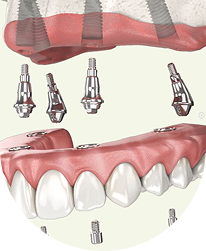

Dantura fixă pe implanturi poate fi o opțiune atunci când lipsa dinților îți afectează confortul zilnic.